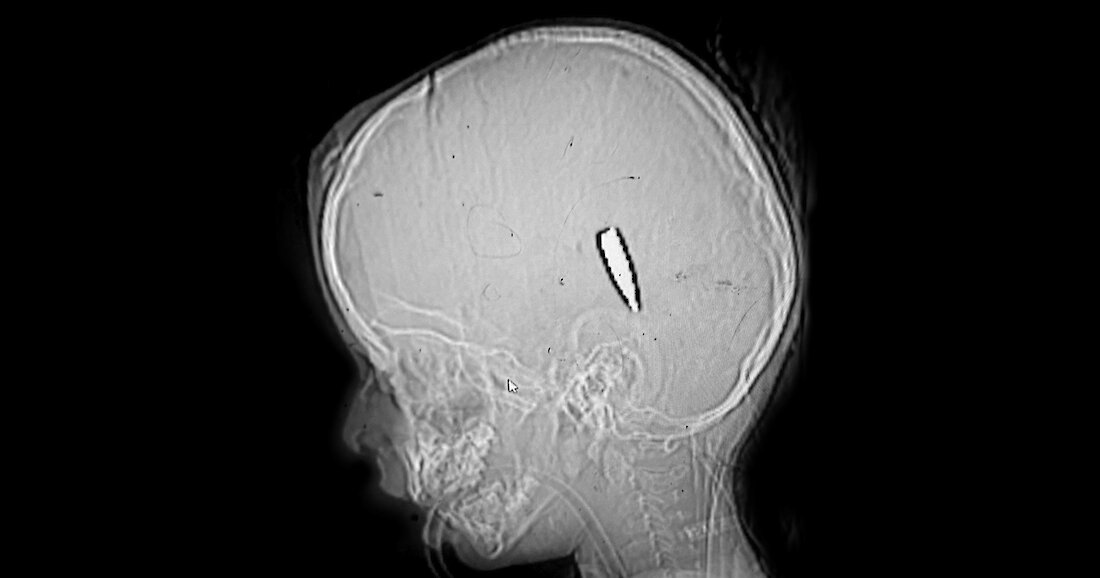

Legalább 114 gyerek halt meg Gázában fej vagy mellkasi lőtt sebekkel, ami már az esetek száma alapján is kizárja, hogy véletlenül történt volna. 15 orvos gyűjtötte össze és elemezte ki a sérüléseiket.

A képen Mira, egy 4 éves kislány röntgen képe.